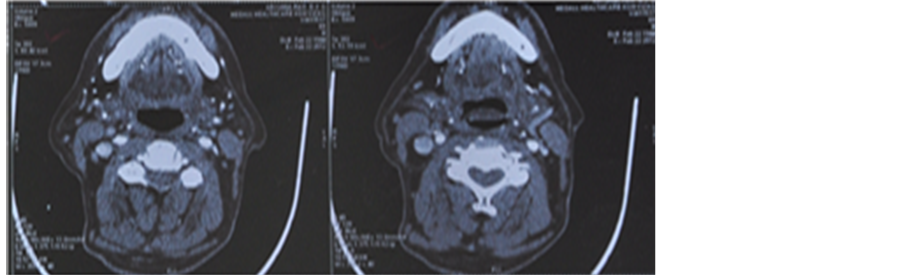

A 72-year-old gentleman presented with swelling on the right side of neck (3.5 cm × 1.8 cm) for 3 months duration. Oral examination showed a growth involving the right side of the soft palate and tonsillar region that was firm on palpation and measured 4 cm × 3 cm approximately. He was diagnosed to have Carcinoma Oropharynx T2N2M0. He received 6 cycles of injection carboplatin 150 mg (in view of high creatinine levels of 1.9 mg) and 200 mg of nimotuzumab along with radiotherapy delivered by IMRT technique to a dose of 6600 cGy/33 fractions/6½ weeks. A follow-up PET scan done after the completion of treatment showed complete regression of primary and nodal disease (Figure 5).

2.6. Case 6

A 73-year-old male patient presented with proliferative growth measuring 4 cm × 3 cm involving the lateral and under surface of anterior 2/3rd tongue with extension on to the floor of mouth. Biopsy of the lesion was moderately differentiated squamous cell carcinoma of tongue. The patient had right submandibular node enlarged and measured 2.5 cm × 2 cm. Patient was planned for weekly carboplatin 150 mg in view of poor general condition and nimotuzumab 200 mg weekly for 6weeks. Patient received radiation dose of 6600 cGy/33 fractions for 6½ weeks by IMRT protocol. Patient had responded well to treatment (Figure 6).

Figure 5. (a) Pretreatment PET CT scan showing 4 cm × 3 cm mass in the right soft palate and the tonsillar region; (b) Post treatment PET-CT scan showing complete regression of primary and nodal disease.

Figure 6. (6a), (6b) and (6c): 2nd week, 3rd week and 4th week of treatment respectively showing tumour regression.